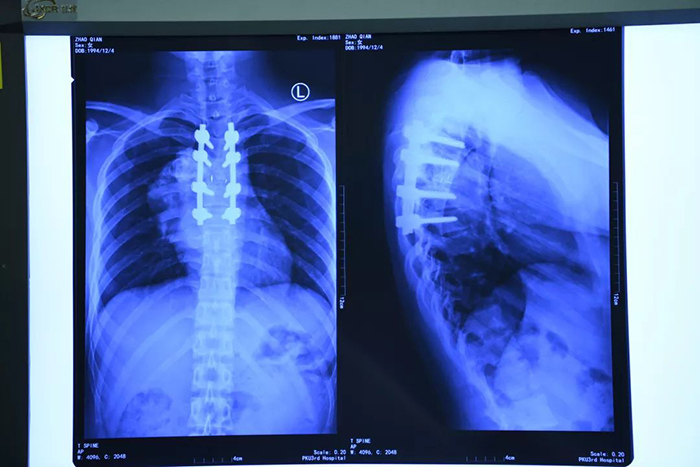

Китайские врачи в Пекине успешно провели хирургическую операцию по замене трех разрушенных опухолью грудных позвонков. Вместо них были поставлены искусственные имплантаты из титанового сплава, изготовленные на 3D-принтере, передает Xinhua.

Известно, что операцию перенесла 25-летняя пациентка. Она позволила избежать развития паралича. По словам врачей, каждый пациент имеет уникальную физиологическую структуру, которая требует лечения в соответствии с его индивидуальностью. Ортопедические, напечатанные на трехмерном принтере имплантаты, по мнению китайских экспертов, должны способствовать развитию производства и снижению медицинских расходов для пациентов.